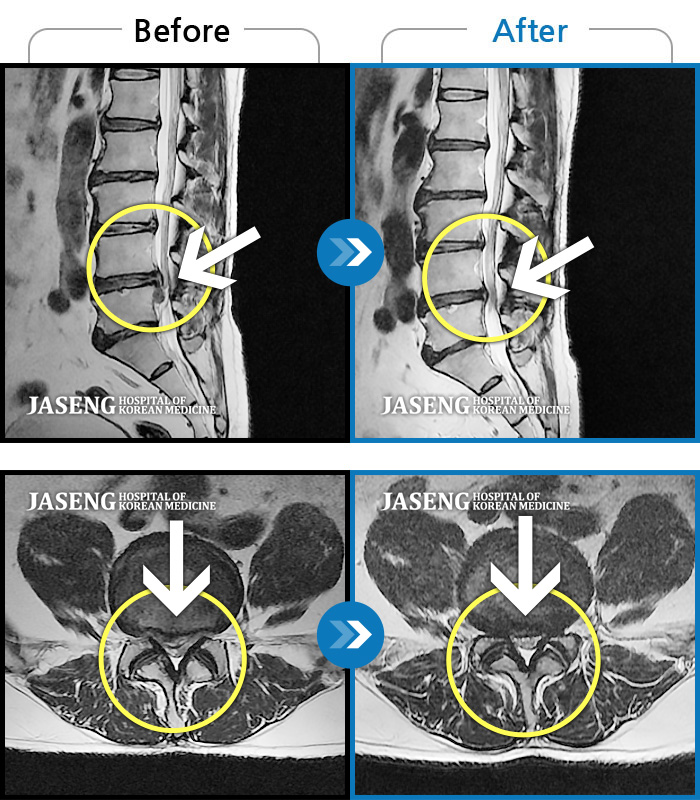

Before

After

환자에게 사전 동의를 받아 동일 조건에서 촬영되었습니다.

개인에 따라 치료 후 부작용이 발생할 수 있으니 의료진과 상담 후 치료를 진행하시기 바랍니다.

허리 및 좌측 하지 통증

허리 및 우측 하지 통증